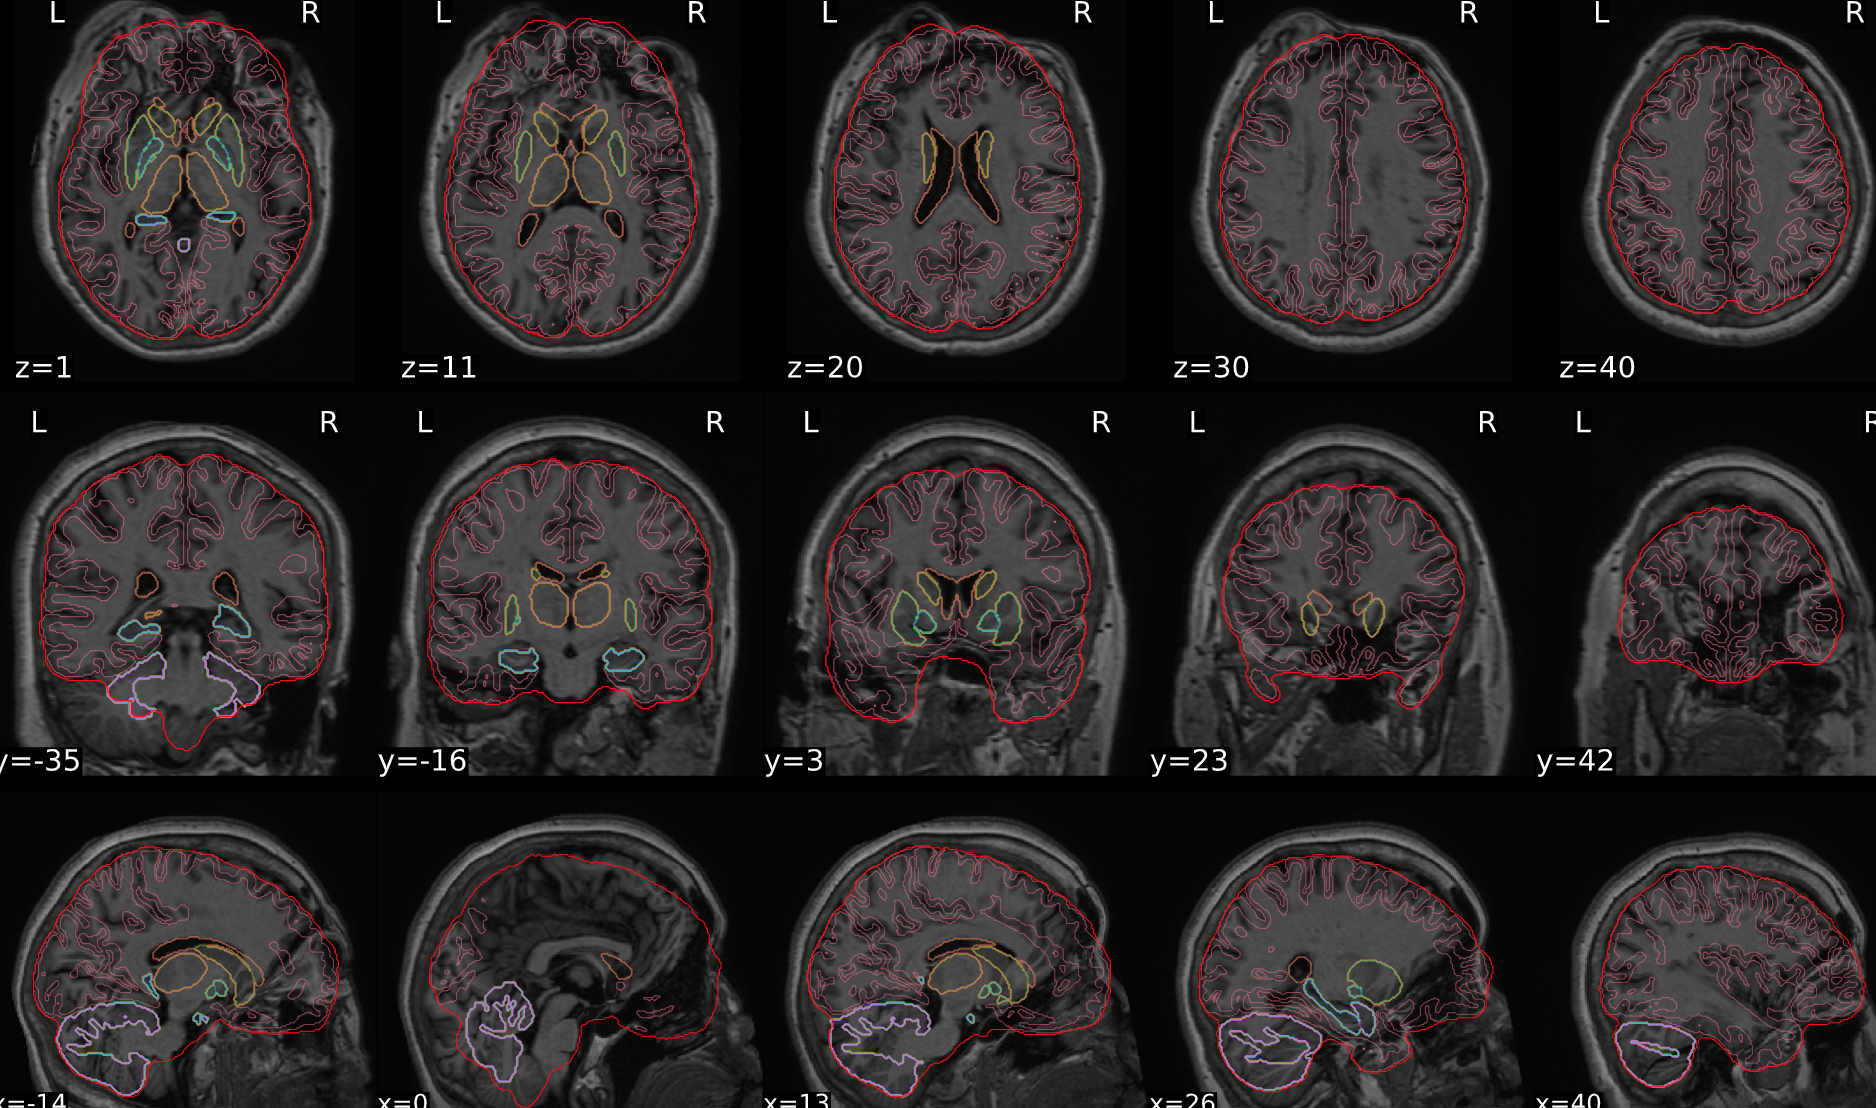

dT1w spatial normalisation

This QC step shows the registration of the T1 image to MNI space.

The registered T1 image is shown in the background with a brain atlas in MNI space as an overlay.

Example of a good subject

- If the registration performed well, you should see an overlap (i.e., correspondence of structures) between the MNI template and the T1 registered to the MNI space.

Example of a bad subject

- In case of poor registration, you should see a misalignment between the MNI template and the T1 (e.g., brain shifted down).

Summary

| good | bad |

|---|---|

| Structures of the MNI template and the registered T1 are well aligned | Structures of the MNI template and the registered T1 aren’t well aligned, e.g. brain is shifted downwards |